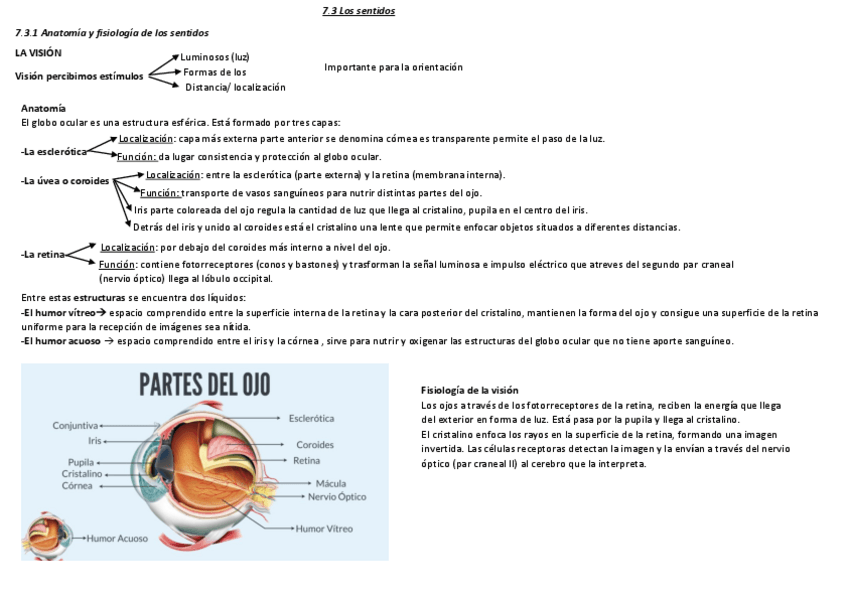

He publicado nuevos apuntes de Fisiopatología general: Tema-7-Fsiopatologia-neurologica.pdf